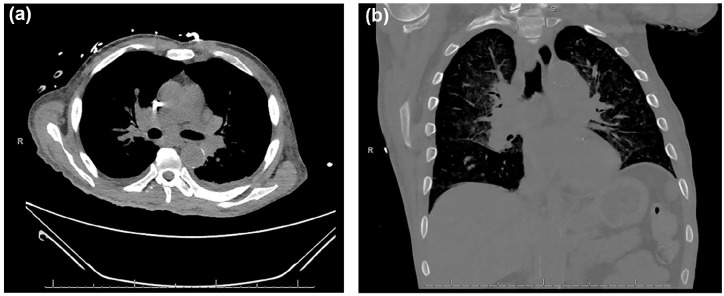

结节病是一种全身性疾病,该病的肺外表现往往无法识别,因为它与许多疾病的表现重叠。终末期肾病(ESRD)可并发高钙血症和脑病,两者都是结节病的潜在症状。这些众多的肺外表现可能延误及时诊断和治疗。在本病例报告中,一名53岁男性ESRD患者在常规血液透析过程中出现无反应发作后入院,后来发现有结节病。最初表现为体温过低、心动过速、白细胞增多和代谢紊乱。支气管肺泡灌洗培养随后生长对甲氧西林敏感的金黄色葡萄球菌,头孢唑林成功治疗。然而,患者仍然患有脑病和高钙血症。进一步检查显示非甲状旁腺激素介导的高钙血症,25-OH维生素D正常,1,25- oh维生素D升高,与结节病、恶性肿瘤或结核病有关。额外的计算机断层成像和支气管超声引导下的活检分别显示淋巴结肿大伴脾肿大和非坏死性肉芽肿,证实结节病的诊断。他开始使用甲基强的松龙、泮托拉唑和甲氧苄啶/磺胺甲恶唑预防耶洛维奇肺囊虫肺炎;血钙水平开始下降,他的精神状态有所改善。虽然他的脑病最初被认为是继发于ESRD和感染,但进一步的检查显示结节病。未经治疗的结节病有显著的健康并发症,包括肺纤维化、肺动脉高压、心律失常和神经功能障碍。由于临床表现可能是多因素的,因此该病例强调了在重症患者的情况下保持广泛区分的重要性。此外,具有复杂病史的患者,如血液透析引起的ESRD,可能使结节病的诊断更加困难。

Sarcoidosis is a systemic disease where extrapulmonary presentation of the disease often goes unrecognized as it overlaps with many disease manifestations. End-stage renal disease (ESRD) can be complicated by hypercalcemia and encephalopathy, both potential signs of sarcoidosis. These numerous extrapulmonary presentations may delay timely diagnosis and treatment. In this case report, a 53-year-old male with ESRD was admitted following an unresponsive episode during routine hemodialysis, later found to have sarcoidosis. Initial presentation notable for hypothermia, tachycardia, leukocytosis, and metabolic derangements. Bronchoalveolar lavage cultures subsequently grew methicillin-sensitive staphylococcus aureus, successfully treated with cefazolin. However, the patient remained encephalopathic and hypercalcemic. Further workup showed nonparathyroid hormone-mediated hypercalcemia with a normal 25-OH vitamin D and elevated 1,25-OH vitamin D, concerning for sarcoidosis, malignancy, or tuberculosis. Additional computed tomography imaging and endobronchial ultrasound-guided biopsy illustrated enlarged lymph nodes with splenomegaly and nonnecrotizing granulomas, respectively, confirming the diagnosis of sarcoidosis. He was started on methylprednisolone, pantoprazole, and trimethoprim/sulfamethoxazole for pneumocystis jirovecii pneumonia prophylaxis; serum calcium levels started to drop, and his mentation improved. While his encephalopathy was initially presumed secondary to his ESRD and infection, further workup revealed sarcoidosis. Untreated sarcoidosis has significant health complications including lung fibrosis, pulmonary hypertension, heart arrhythmias, and neurological deficits. This case highlights the importance of maintaining a broad differential in the setting of critically ill patients as clinical presentations can be multifactorial. Furthermore, patients with a complex medical history such as ESRD on hemodialysis can make concluding sarcoidosis as a diagnosis more difficult.